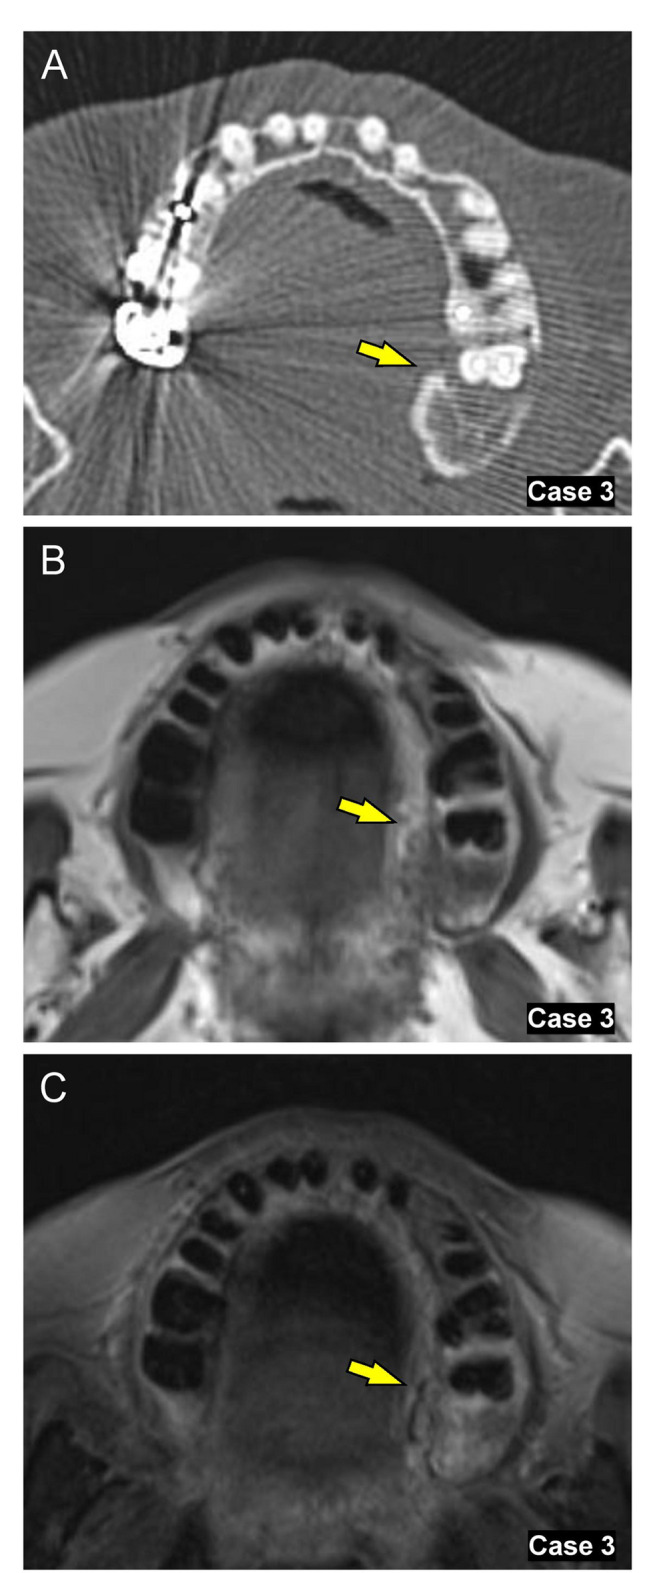

Objectives: Microbial infections can influence destructive jawbone lesions, yet the role of Entamoeba gingivalis (E. gingivalis) in these lesions is poorly understood, particularly when co-infected with Actinomyces. This study introduces a novel clinicopathological perspective on jawbone destruction linked to E. gingivalis and Actinomyces co-infection, aiming to improve diagnosis and treatment. In this study, we tried to evaluate minimally invasive methods for improving diagnosis and treatment for jawbone destruction, possibly linked to E. gingivalis and Actinomyces co-infection. We analyzed 11 cases of jawbone destructive lesions observed in patients (ages 42 to 83, both female and male) who visited Tohoku University Hospital from January 2015 to December 2021, in which scraping cytology detected E. gingivalis and Actinomyces.

Materials and methods: We thoroughly assessed clinical symptoms, imaging findings, and treatment outcomes, including the duration of antimicrobial therapy, to identify distinctive patterns associated with this co-infection.

Results: On imaging, patients exhibited significant mandibular resorption and sclerosis, despite the absence of typical symptoms of osteomyelitis or actinomycosis. Notably, E. gingivalis alone was linked to faster wound healing and shorter antimicrobial therapy durations compared to cases with concurrent Actinomyces infection (p = 0.011). The use of minimally invasive procedures, focusing on removing necrotic bone and loose teeth, led to effective healing and rapid recovery across all cases, offering promising prospects for enhanced treatment outcomes.